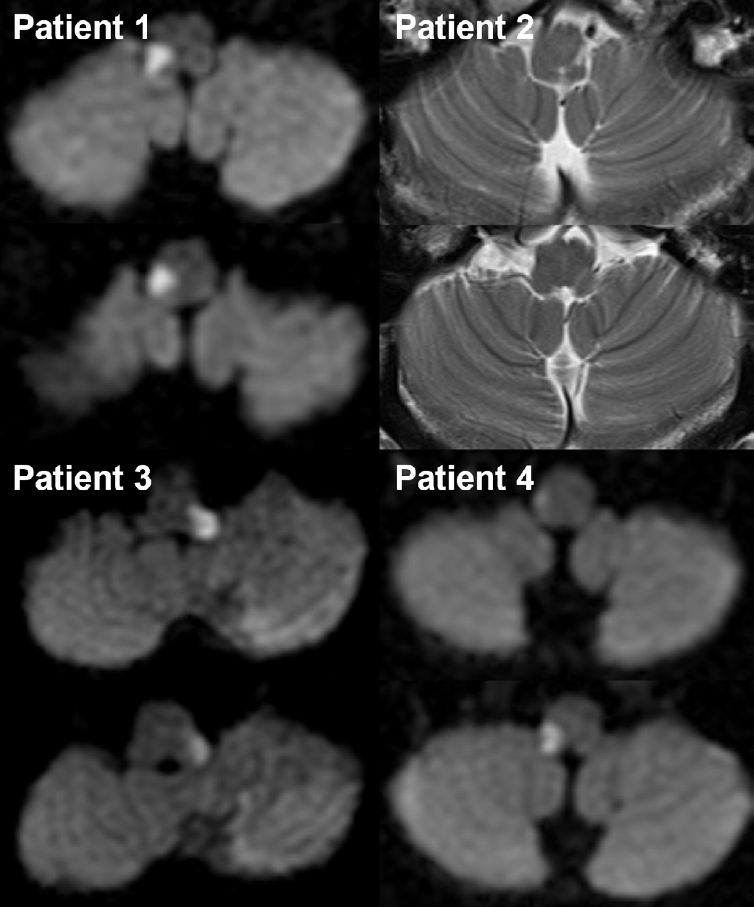

Figure 1.

Neuroimaging of the four patients who presented with dorsolateral medullary infarction.

Diffusion-weighted (patients 1, 3, and 4) or T2-weighted (patient 2) brain magnetic resonance imaging shows high signal intensity lesions involving the unilateral dorsolateral medulla. An additional lesion in the ipsilateral cerebellar hemisphere is also observed in patient 3.

Among the 231 patients diagnosed with dorsolateral medullary infarction during the study period, 204 completed at least 6 months of follow-up after the index stroke and were eligible for analysis. Of these, four patients (three males; mean age, 58.3±8.4 years; 4/204 [1.96%]) developed headache syndromes consistent with TACs and were included in this study. Baseline demographics, characteristics of the index stroke, MRI-identified lesions, and headache characteristics are summarized in Table 2 and Figure 1. All patients exhibited either stabbing (50%) or electric shock-like pain in the ipsilateral periorbital, hemifacial, and temporal regions. Headaches developed 2.5 to 4 months after the initial infarction (mean, 3 months) with brief attacks lasting 1–2 minutes, occurring 1–5 times daily. Lacrimation (100%) and conjunctival injection (75%) were common cranial autonomic symptoms, all of which were observed on the ipsilateral side. According to the diagnostic criteria of ICHD-3, three patients (75%) were compatible with a SUNCT diagnosis, while one experienced SUNA, rather than a typical trigeminal neuralgia (TN) or cluster headache. The headaches persisted for several years in three patients (75%) despite empirical treatment with medications including gabapentin, amitriptyline, or lithium.